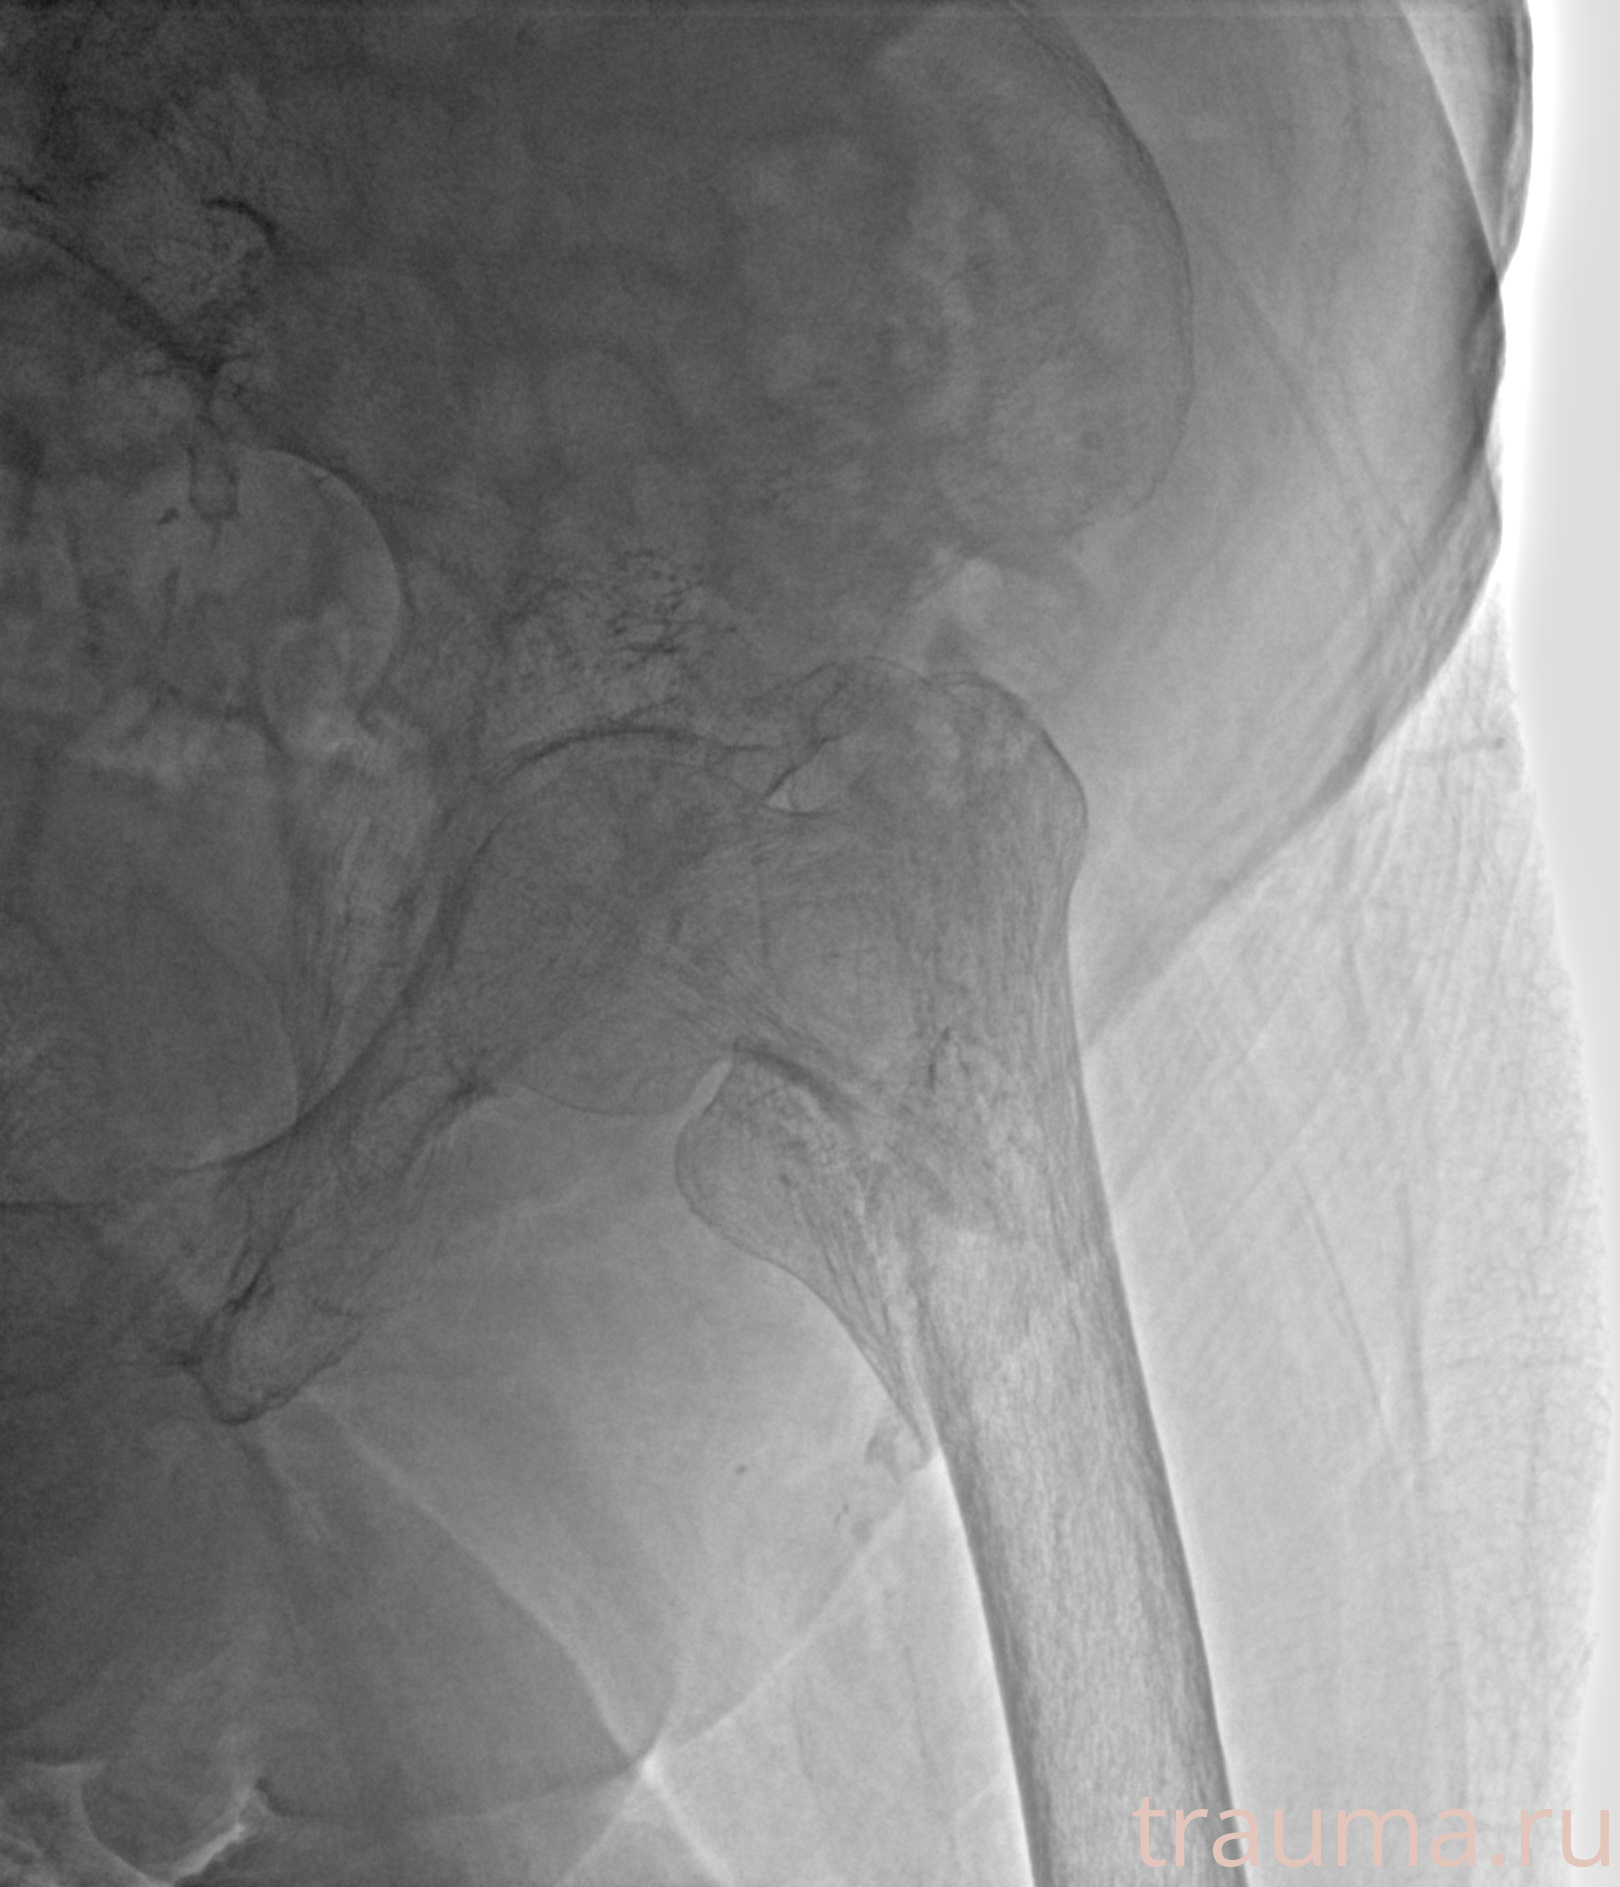

Рентгенограммы

Рентген на дому: по вашему адресу приезжает врач-рентгенолог, травматолог-ортопед с мобильным рентгеновским аппаратом, проводит диагностику травмы или заболевания, делает необходимые рентгенограммы, дает рекомендации по дальнейшему лечению. Получить качественные снимки в домашних условиях возможно благодаря уникальной методике, разработанной МосРентген Центром для института  Склифосовского